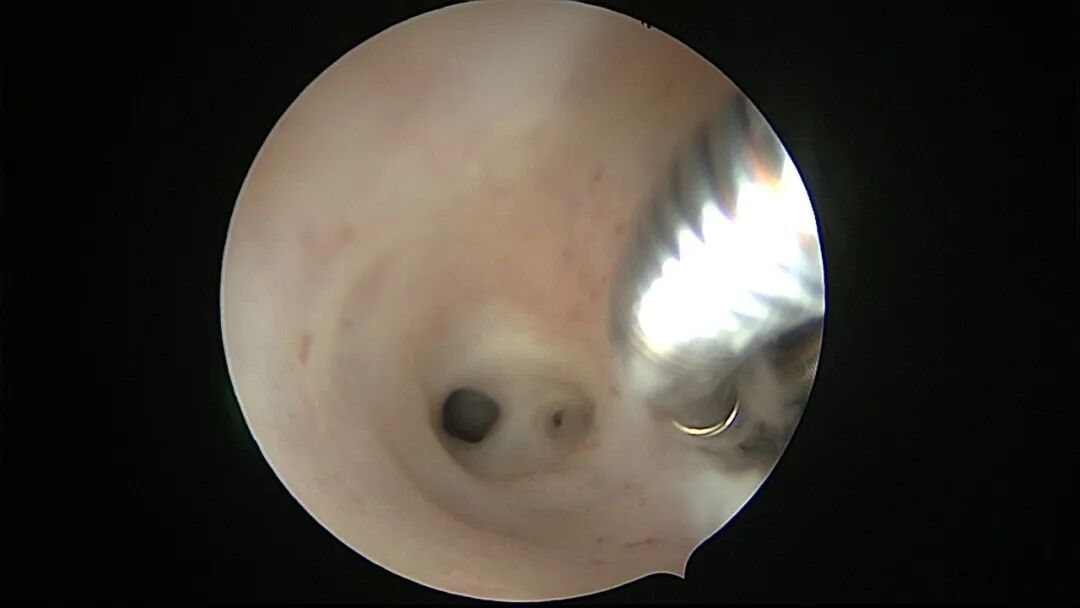

第一次宫腔镜:2021年4月,闭经50+天,B超提示宫腔粘连,宫腔镜探查见宫颈管上段封闭粘连,宫腔广泛粘连,AFS评12分(最高分)。宫腔镜单极电切分粘,恢复宫腔形态,显露双侧输卵管开口,右侧宫角附近内膜柔软、红润,宫腔防粘连复发处理。